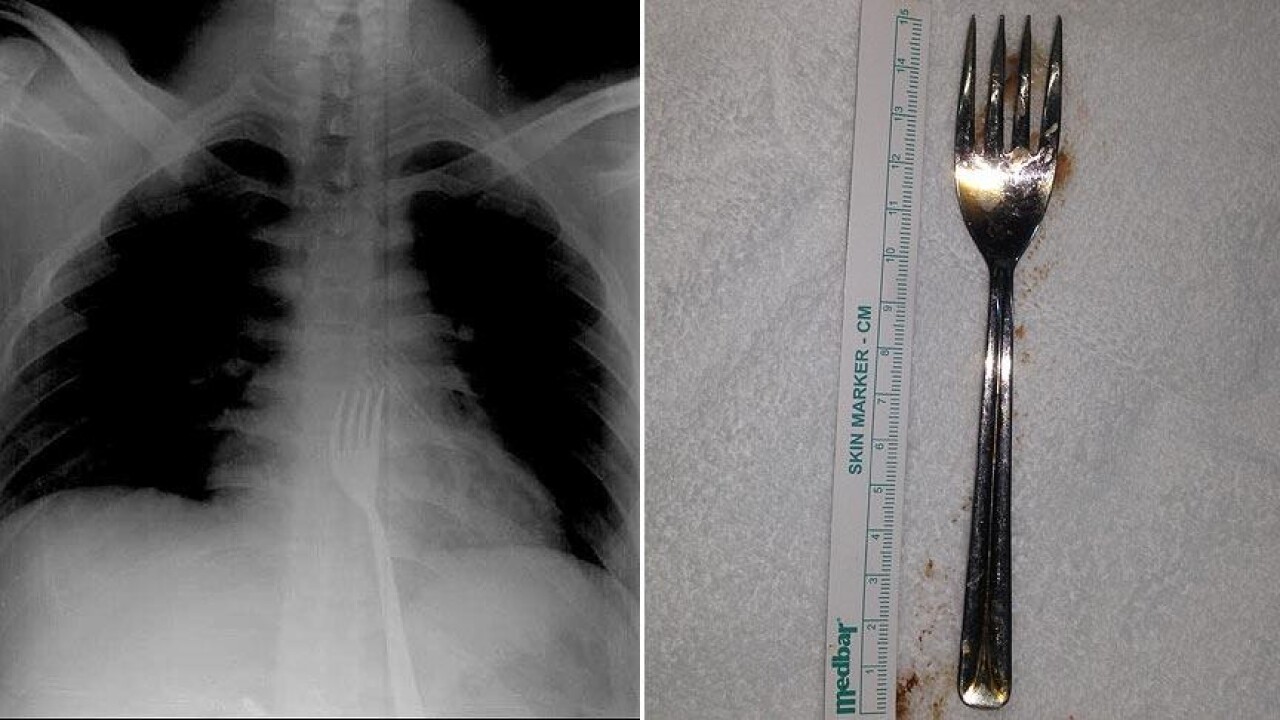

Burada röntgeni çekilen hastanın yemek borusunda 18 santimlik çatal olduğu tespit edildi.

Vakayı ilk duyduğunda şaşırdığını anlatan Edizsoy, "Büyük bir çatalın tamamen yutulması şeklinde ortaya çıkan bu vakayı ilk duyduğumda doğru olmadığını düşündüm. Hasta 18 yaşında ve yabancı uyrukluydu. Türkçesi biraz zayıf olduğu için belki de yanlış anlaşılmalar olabileceğini düşündük. Ama hastanın filmini çektiğimizde gerçekten bir çatalın yemek borusunda olduğunu gördük." dedi.